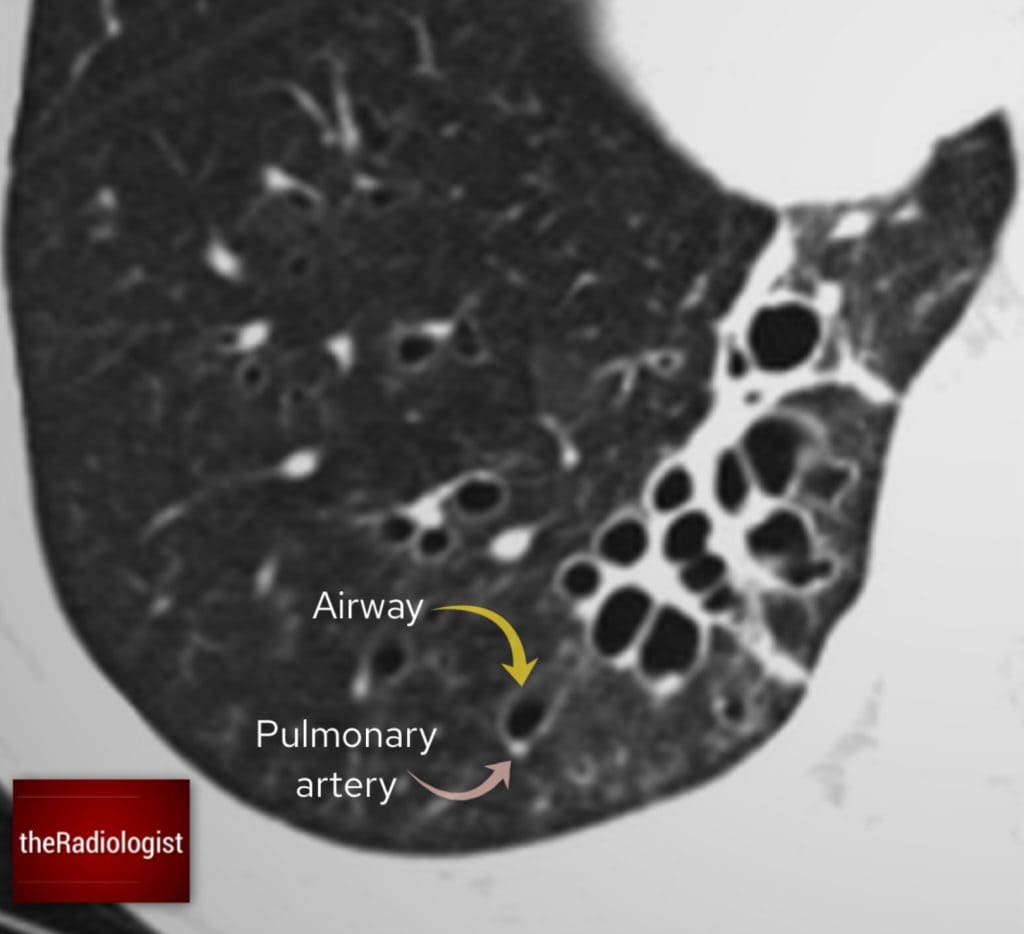

A CT scan is the gold standard because it lets us see the airway size and structure more clearly. Normally, the airway should be the same size or smaller than the pulmonary artery running alongside it. In bronchiectasis, the airway is larger than the adjacent pulmonary artery. On CT scans this can give something called a ‘signet ring’ sign.

In normal circumstances the airway should be smaller or the same size as the pulmonary artery running beside it. I often think can I fit the pulmonary artery into the airway as if it were a hole – if I can’t then there is no bronchiectasis.